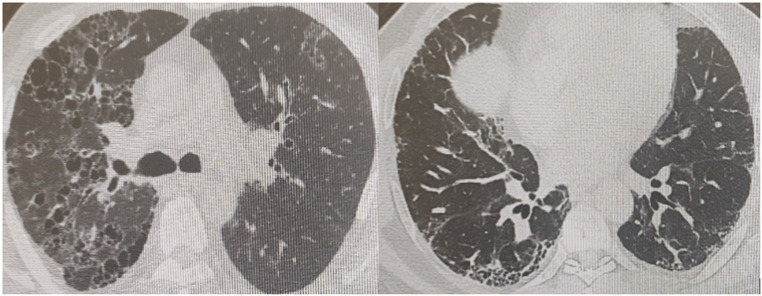

目的:间质性肺疾病(ILD)是自身免疫性风湿性疾病(ARDs)中最具挑战性的疾病之一,可导致显著的发病率和死亡率。在这篇文章中,三级风湿病学和肺病学中心的合作工作描述了ARD合并ILD (ARD-ILD)患者的人口学、血清学和放射学结果。方法:一项描述性、回顾性研究,并从研究参与者的图表中收集有关ILD的人口统计学、临床、实验室、放射学或组织病理学发现的数据。结果:约212例ARD-ILD患者被评估。其中女性172例(81.1%),男性40例(18.9%)。风湿病的分布如下:系统性硬化症114例(53.8%),类风湿关节炎47例(22.2%),Sjögren综合征14例(6.6%),炎性肌病16例(7.5%),自身免疫性间质性肺炎9例(4%),未分化结缔组织病8例(3.8%),系统性红斑狼疮4例(1.9%)。根据影像学表现,71.7%的患者为非特异性间质性肺炎(NSIP), 13.7%的患者为明确的普通间质性肺炎(UIP), 8.5%的患者为可能的间质性肺炎,3.8%的患者为淋巴细胞性间质性肺炎,1.9%的患者为组织性肺炎,0.5%的患者为不典型肺炎。结论:本研究显示导致ILD的最常见的风湿病仍然是系统性硬化症,而NSIP作为影像学表现更为突出。IPAF是近年来进入文献的一种疾病,也是一种重要的ILD类型。鉴于ARDs涉及多系统,不同学科之间的合作无疑对这些疾病的诊断和管理至关重要。

Objective: Interstitial lung disease (ILD) is one of the most challenging involvement of autoimmune rheumatic diseases (ARDs) and could lead to significant morbidity and mortality. In this article, a collaborative work of tertiary rheumatology and pulmonology centers describing demographic, serological, and radiological findings of patients with ARD associated with ILD (ARD-ILD) is presented. Methods: A descriptive, retrospective study, and data related to demographics, clinical, laboratory, radiologic, or histopathological findings of ILD were collected from the study participants' charts. Results: Around 212 patients with ARD-ILD were evaluated. Of the patients, 172 (81.1%) were female and 40 (18.9%) were male. The distribution of the rheumatic diseases was as follows: systemic sclerosis in 114 (53.8%), rheumatoid arthritis in 47 (22.2%), Sjögren's syndrome in 14 (6.6%), inflammatory myopathy in 16 (7.5%) patients, interstitial pneumonia with autoimmune features (IPAF) in 9 (4%) patients, undifferentiated connective tissue disease in 8 (3.8%), and systemic lupus erythematosus in 4 (1.9%). According to the radiological patterns, 71.7% of the patients had nonspecific interstitial pneumonia (NSIP), 13.7% had definite usual interstitial pneumonia (UIP), 8.5% had probable UIP, 3.8% had lymphocytic interstitial pneumonia, 1.9% had organizing pneumonia, and 0.5% had an atypical pattern. Conclusion: This study showed that the most common rheumatic disease causing ILD is still systemic sclerosis, and NSIP is more prominent as a radiological pattern. IPAF, a disease that has entered the literature in recent years, is also an important type of ILD. Given the multisystemic involvement of ARDs, collaboration among different disciplines is undoubtedly crucial in the diagnosis and management of these diseases.